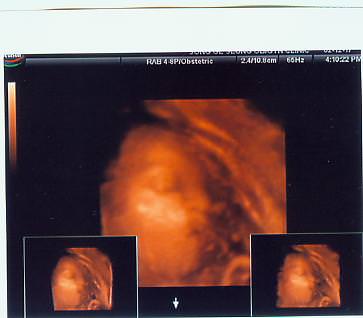

산책할려고 했는데 눈이 와서 엄청춥네요^^

울짱구 저만보면 뽀뽀만 해용~~(자랑)^^